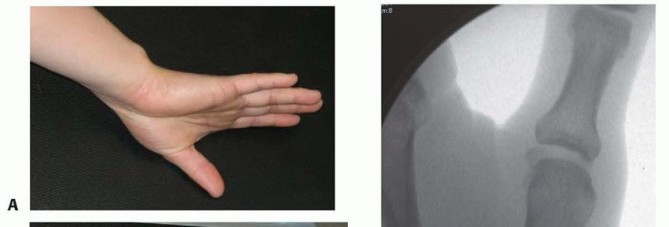

Fracture Patterns and Buchler Zones

These deforming forces lead to classic intra-articular fracture-dislocation patterns. The Bennett Fracture is a two-part intra-articular fracture where the metacarpal shaft is radially and dorsally displaced by the pull of the APL. Crucially, a small, intact ulnar fragment remains at the base of the thumb metacarpal, held perfectly reduced by the strong volar beak ligament. The Rolando Fracture represents a more complex, comminuted intra-articular fracture involving the base of the thumb metacarpal, classically presenting as a T or Y-type pattern. By definition, no portion of the metacarpal shaft remains in continuity with the CMC joint, rendering it profoundly unstable.

Image

Buchler et al. elegantly described three critical zones at the base of the thumb metacarpal, which guide our understanding of stability and operative indications. Zone 1 encompasses the volar aspect of the joint, typically involving the beak ligament avulsion. Zone 2 represents the central, normally loaded portion of the joint; involvement here is absolutely critical for load transfer and stability, almost universally mandating operative intervention. Zone 3 encompasses the dorsal aspect of the joint. Understanding these zones allows the surgeon to conceptualize the fracture in three dimensions and plan the trajectory of internal fixation devices accordingly.